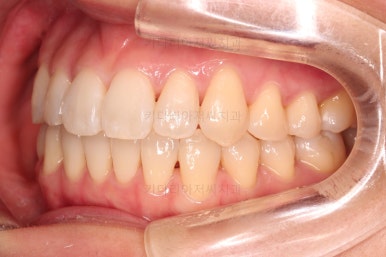

1. 초진

초진 시 입안의 모습입니다.

덧니가 눈에 띄고요.

맞물림이 긴밀하지 못한 상태였습니다.

전반적으로 약간 삐뚤지만 많이 심하다고 보긴 힘들었습니다.